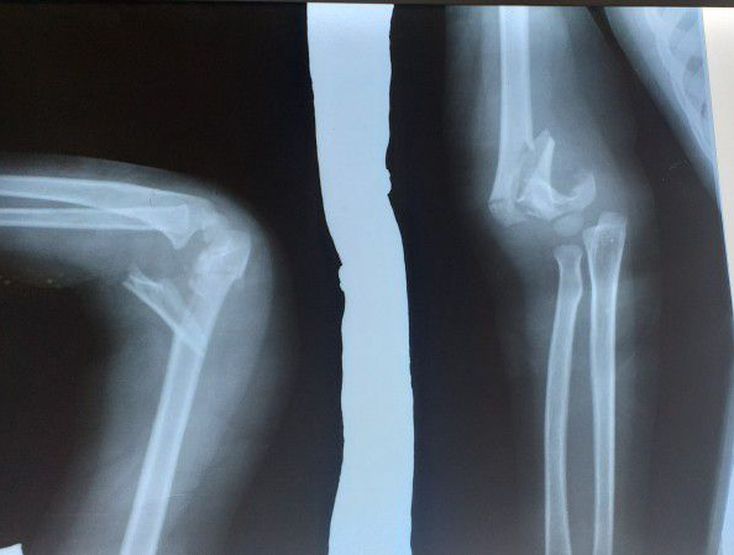

Whic bone is broken and what manage operation or stablishing

Medial epicondyle of the humerus is broken